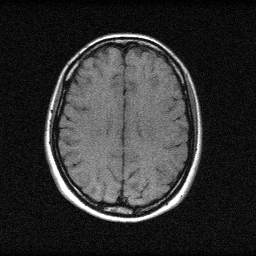

Reconstruction Gallery — 4 Scenes × 3 Scenarios

Ground Truth

Measurement

Reconstruction